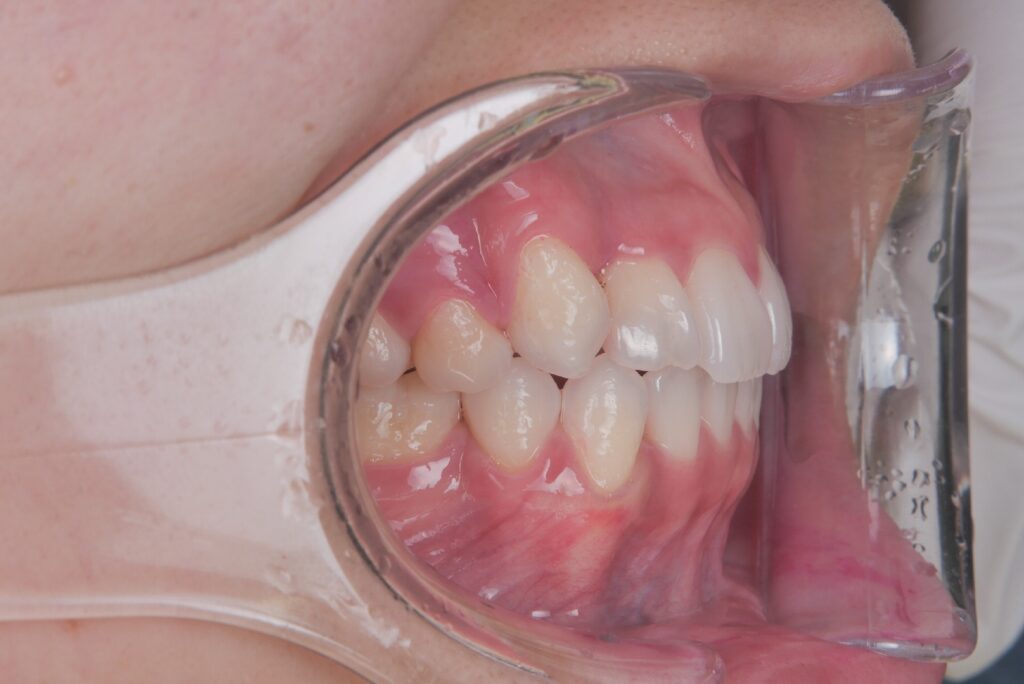

例えばこのケースは、重度のガタガタで、通常であれば抜歯矯正を選択したいケースでしたが、横顔がきれいなEラインであったので、これ以上下げると、若い時はいいのですが、お年を召されて、ほうれい線がめだったり、よく巷で言われる老人様顔貌になることが予測されたため、3次元のCT写真で正確に診断し、非抜歯で仕上げたケースになります。

重度のガタガタでしたが、抜歯矯正でなく、非抜歯矯正で治療することで、歯並びはもちろんのこときれいな横顔のまま、今日治療を終了することができたケースになります。